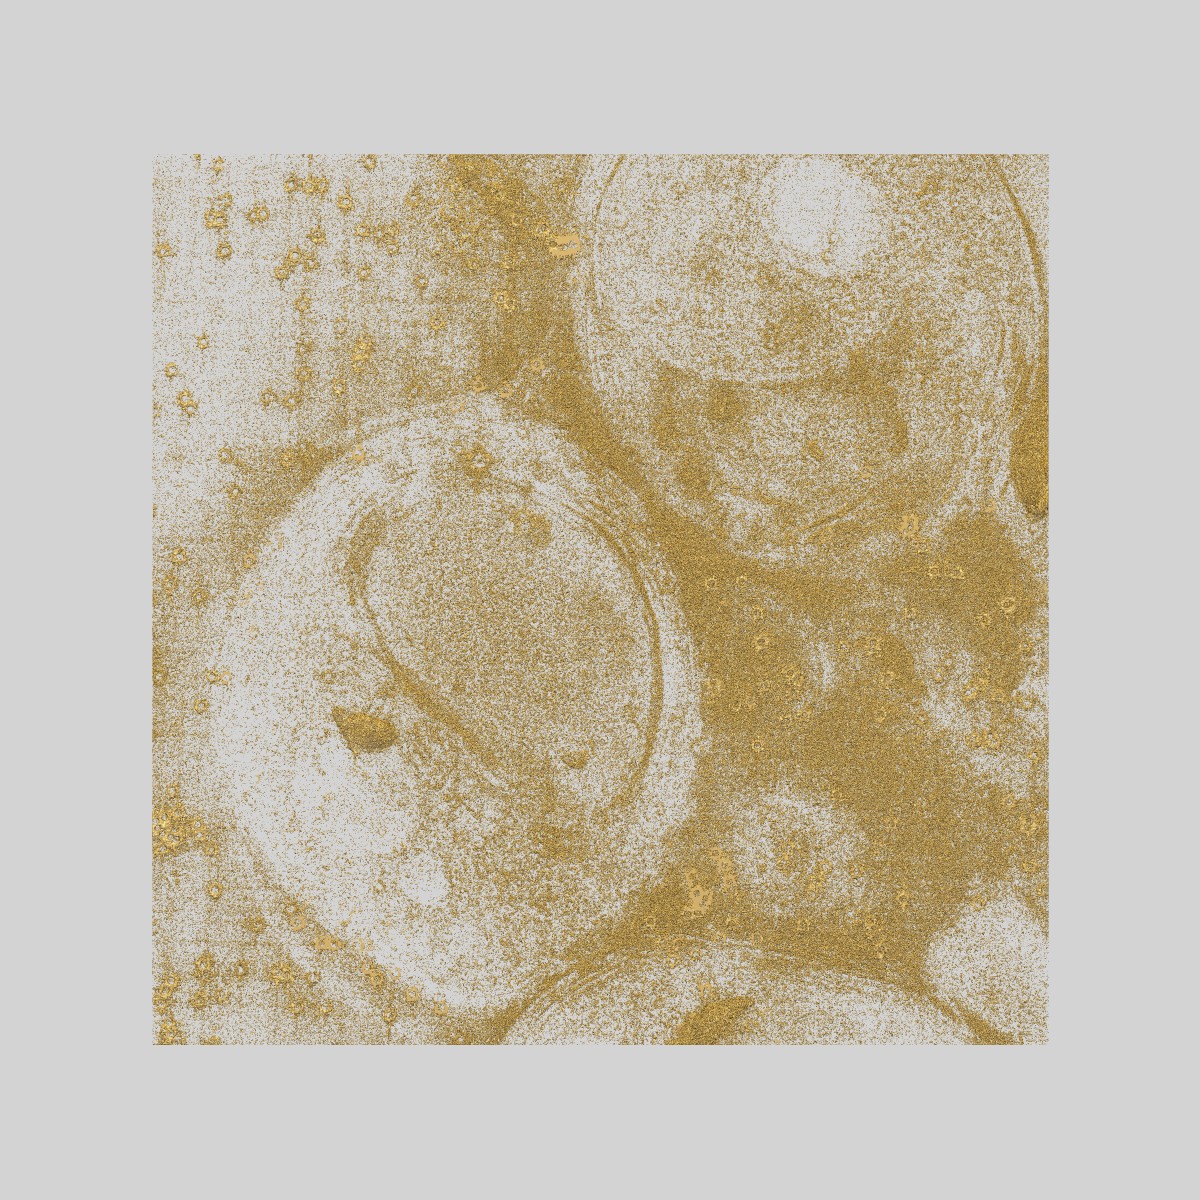

Malaria-infected red blood cell section showing schizont stalled in egress with the inhibitor E64

Sample Organism: Plasmodium falciparum 3D7

Sample: Plasmodium falciparum infected human erythrocyte treated with the egress inhibitor E64

Parasitophorous vacuole poration precedes its rupture and rapid host erythrocyte cytoskeleton collapse in Plasmodium falciparum egress.

Hale VL , Watermeyer JM, Hackett F, Vizcay-Barrena G, van Ooij C, Thomas JA , Spink MC, Harkiolaki M, Duke E, Fleck RA , Blackman MJ, Saibil HR

(2017) PNAS , 114 , 3439 - 3444